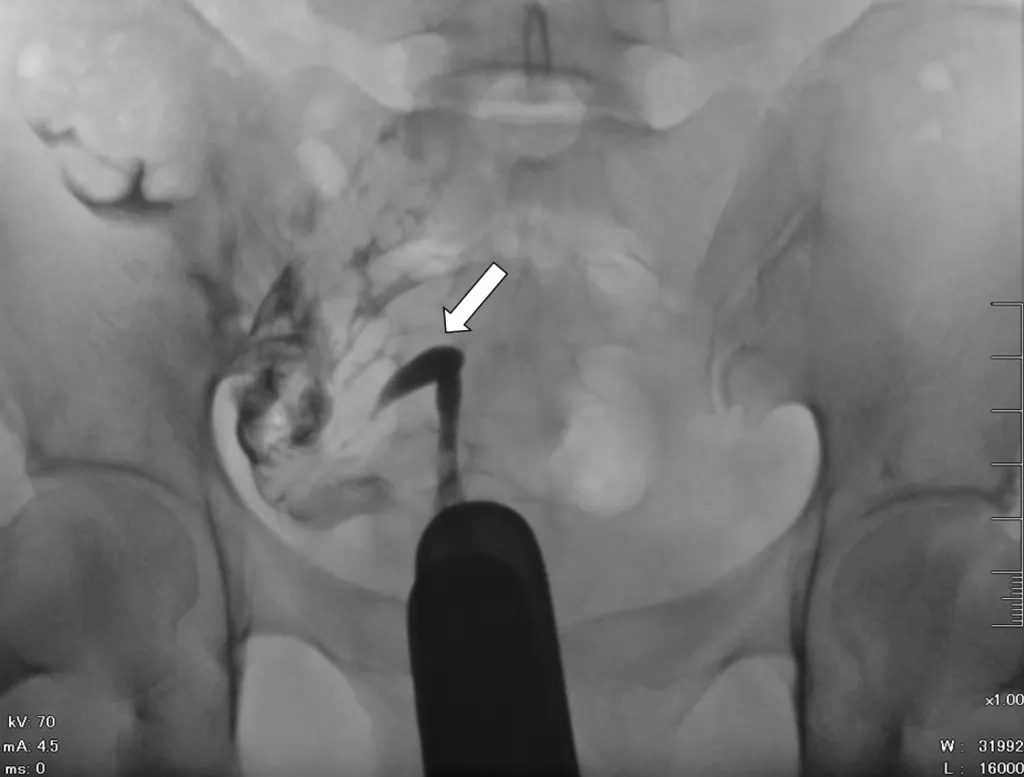

破題關鍵

這張子宮輸卵管攝影(HSG)顯示子宮腔只有單側發育,呈現細長彎曲的香蕉狀,且只有一側輸卵管顯影,這是典型的單角子宮特徵。